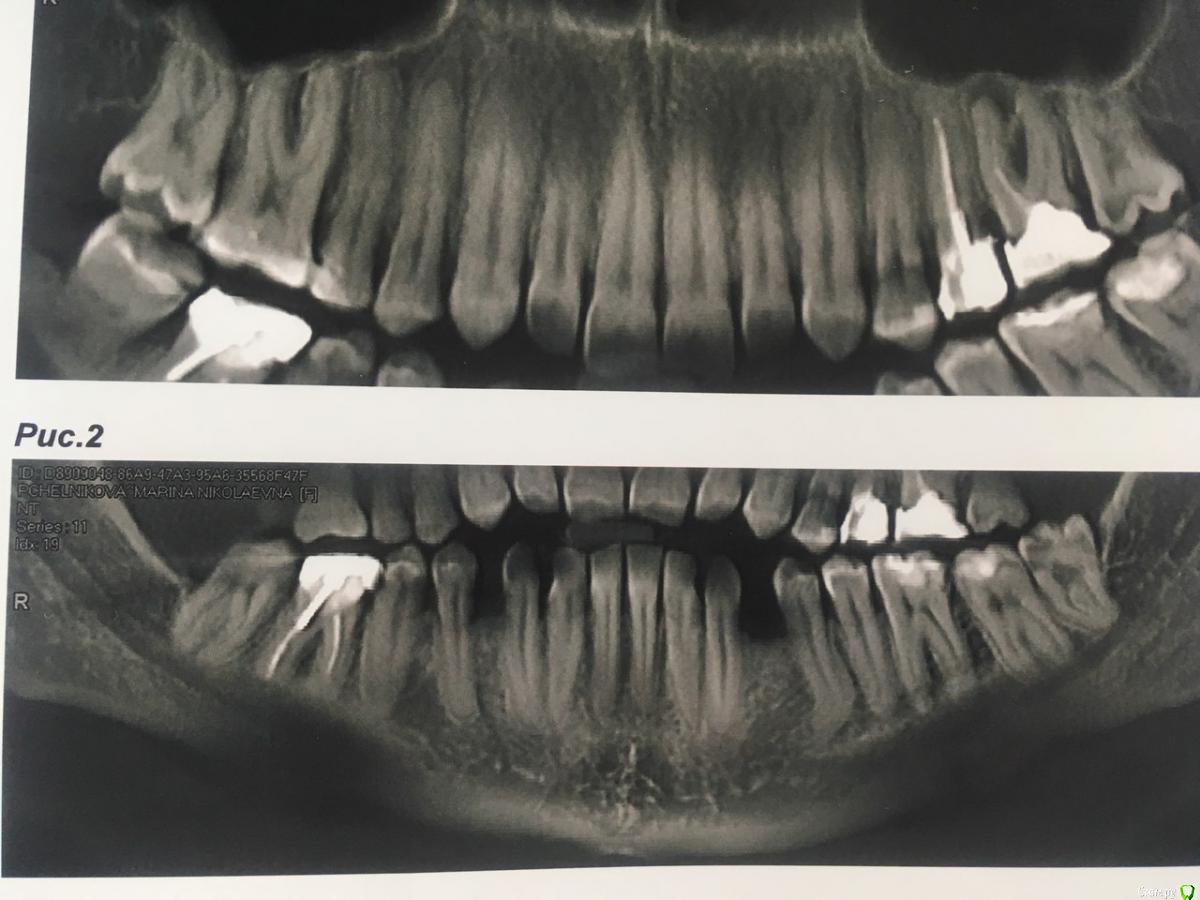

И вот уже несколько лет нижняя 6-ка периодически ноет (особенно если остыть),каждый год ходила  к одному хирургу,готовясь  уже удалить этот источник неприятных ощущений, но каждый раз врач делая р.снимок говорил все нормально.

В течении  года от зуба опустилась десна и там проглядывается прозрачно-черный корень и очень быстро на 5 и 4-ки обазовались черные пятна.  Сделала КТ. Теперь стоит вопрос долгое  лечение или удаление.Врач говорит все будет видно при вскрытии. Если лечение то долгое и без гарантий.   Мне кажется от корня там мало что осталось,судя по цвету и по тому как быстро испортились рядом стоящие зубы. Может проще не лечить,установить имплант?

Правда один врач сказал,что то вроде убыли костной ткани и имплант удержать будет не чем,кроме того сужение верхней челюсти, рецессия десны и стирание в пришеечной области из за прикуса. В заключении кт -пародонтопатия легкой степени тяжести.

соглашусь, решение нужно принимать после оценки объема оставшихся твердых тканей и перспективы протезирования. Если судить только по снимкам, то скорее удалять...